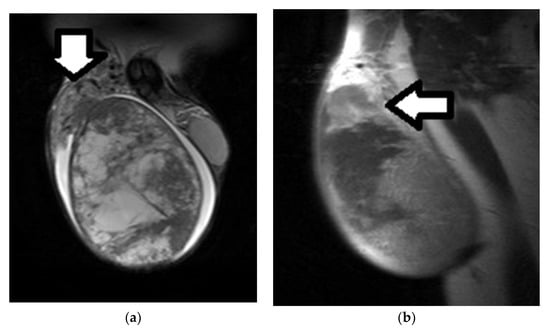

3.1. MRI Findings of TGCTs

3.2. Epidermoid Cysts

3.3. Testicular Lymphoma